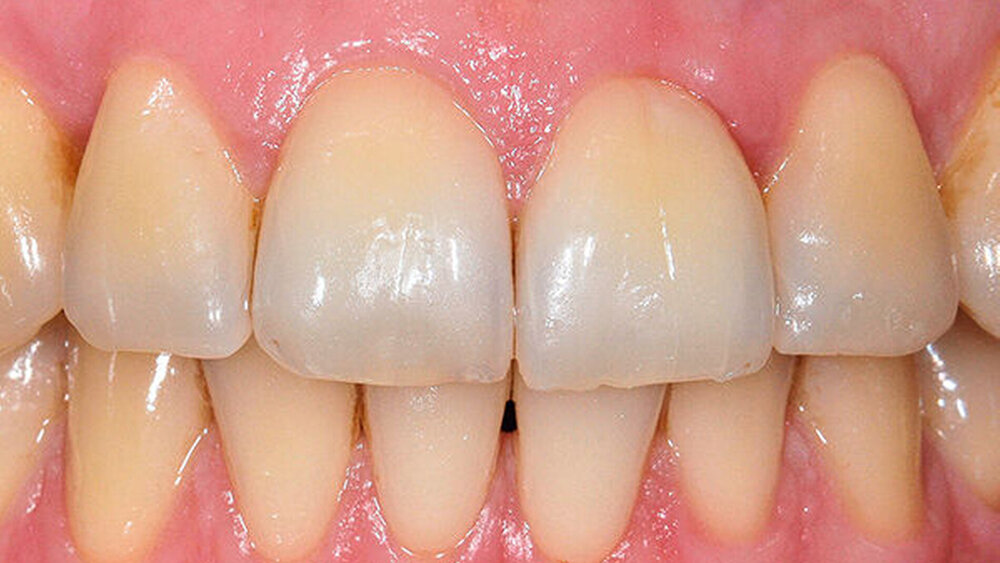

Vier Wochen nach dieser Initialsitzung wurde eine subgingivale Instrumentierung aller pathologisch vertieften Taschen durchgeführt („Full Mouth Disinfection“). Bei der Reevaluation acht Wochen nach antiinfektiöser Therapie waren die klinischen Anzeichen einer parodontalen Entzündung verbessert. Persistierende Sondierungstiefen ab sechs Millimeter mit Bluten auf Sondierung wurden nur noch an 12 distal festgestellt (Abb. 2).